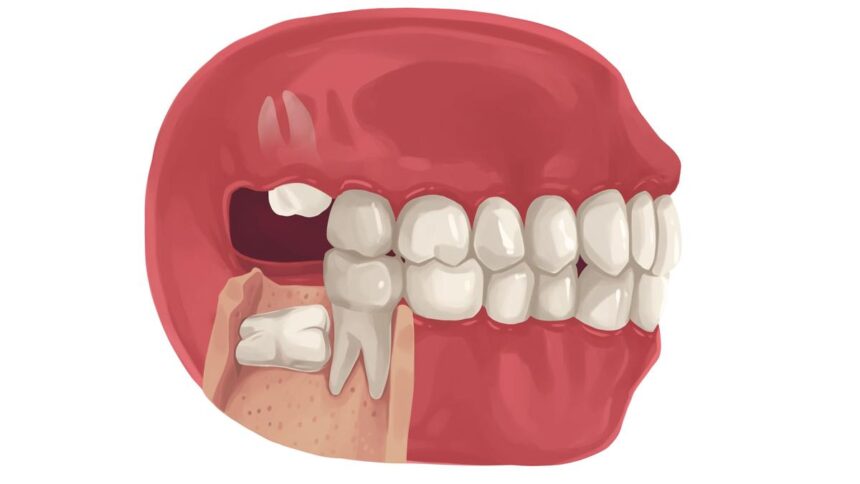

The primary motive knowledge tooth trigger issues is as a result of there’s usually not sufficient area in your mouth for them to suit. This can be a situation generally known as an impacted knowledge tooth, the place the tooth can turn into trapped beneath the gums and bone tissue, leading to issues similar to ache, periodontal illness, tooth decay, an infection, tooth decay, and injury to close by tooth. As a result of they’re situated at the back of the mouth, they’re tough to wash and might trigger issues.

Knowledge tooth can turn into partially or fully impacted. Partially impacted knowledge tooth have some progress and might be seen, whereas totally impacted knowledge tooth are fully buried beneath the gums.